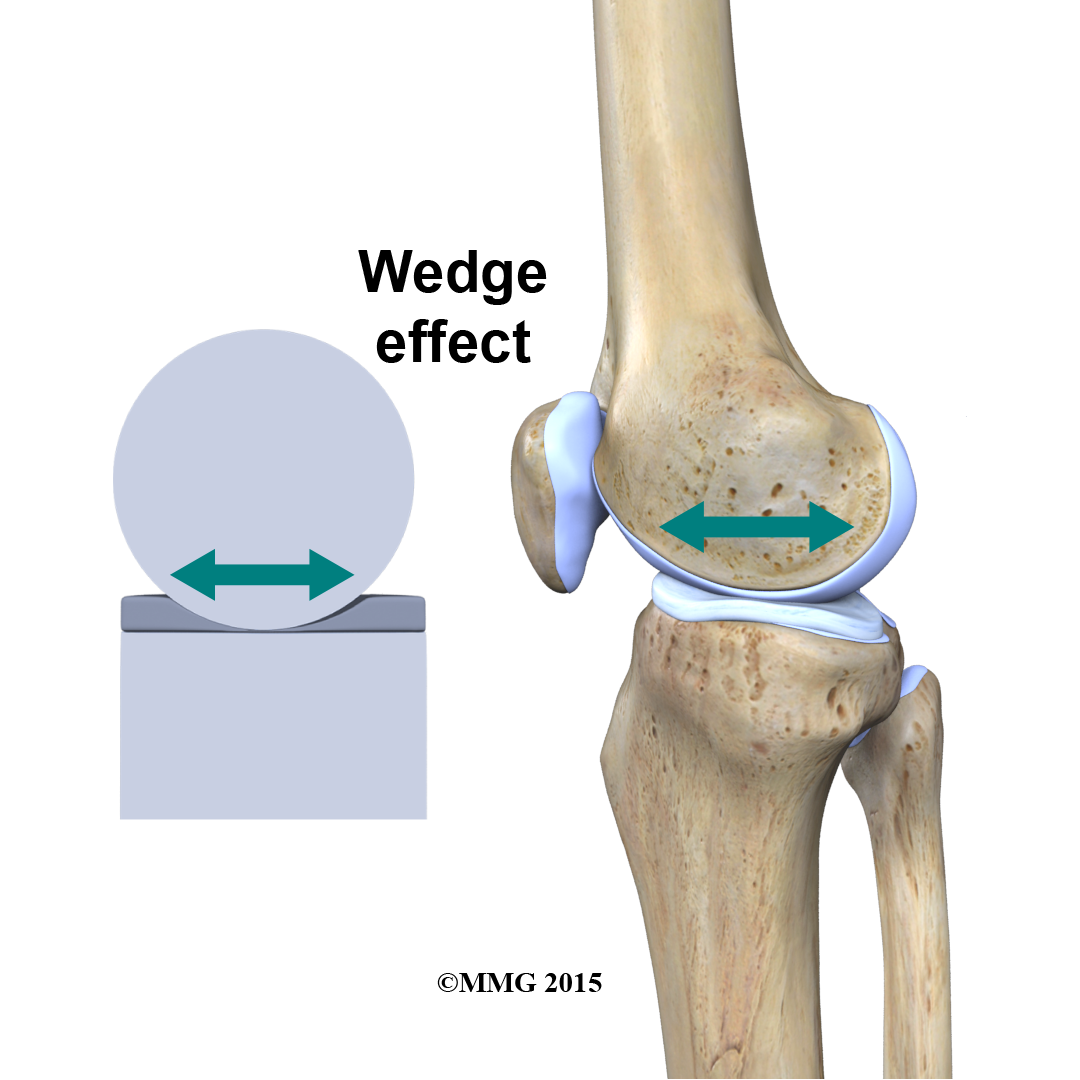

In addition to protecting the articular cartilage, the menisci help the ligaments with stability of the knee. The menisci make the knee joint more stable by acting like a wedge set against the bottom of a car tire. The menisci are thicker around the outside, and this thickness helps keep the round femur from rolling on the flat tibia. The menisci convert the tibial surface into a shallow socket. A socket is more stable and more efficient at transmitting the weight from the upper body than a round ball on a flat plate. The menisci enhance the stability of the knee and protect the articular cartilage from excessive concentration of force.